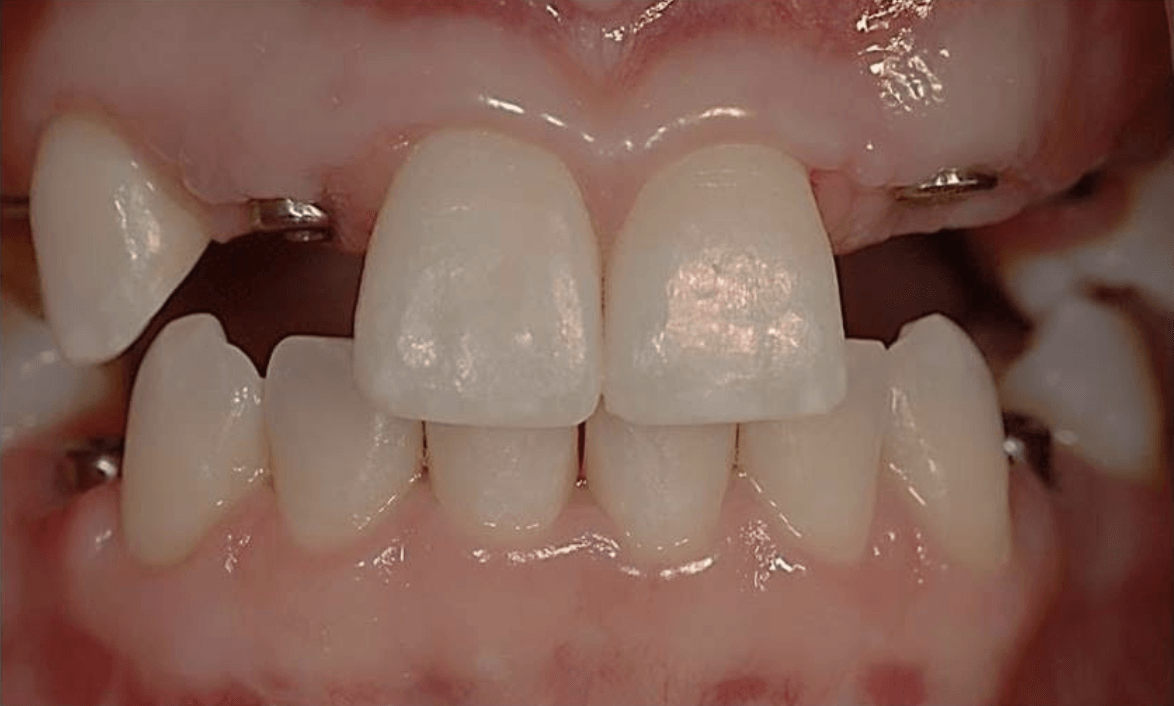

Porcelain Crowns

This patient was unhappy with the short length and discolouration of her teeth. We did a wax up study to evaluate the ideal size and length for her teeth. We then proceeded with six anterior porcelain crowns.